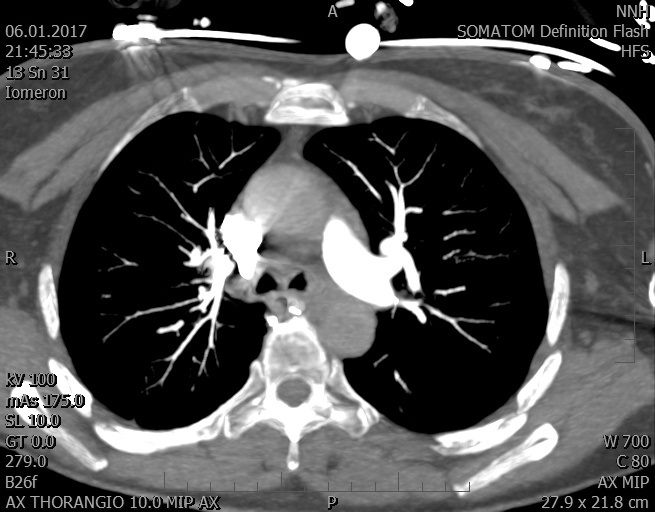

Video 2 - Echokardiograficky byla zjištěna těžká dysfunkce dilatační levé komory s nezvětšenou pravou komorou.Pro nejasnou příčinu zástavy jsme provedli i vyšetření výpočetní tomografií (CT), které vyloučilo plicní embolizaci (série 1 - soubory na konci článku). V den přijetí při přetrvávající oběhové nestabilitě byla nemocná opakovaně defibrilována pro fibrilaci komor se stabilizací rytmu po podání amiodaronu a mesocainu. Dle hemodynamických měření se jednalo o těžký kombinovaný šok. Vstupní laboratorní vyšetření bylo bez větších pozoruhodností. Posléze jsme doplnili anamnézu od příbuzných a zjistili, že pacientka užila do dvou hodin před srdeční zástavou první tabletu amoxicilinu na lehký respirační infekt. Při nevýtěžnosti vstupních vyšetření a nových anamnestických informacích jsme doplnili 14 hodin po kolapsu vyšetření koncentrace tryptázy v séru, která byla extrémně zvýšena (tabulka 2), což nás vedlo k podezření na anafylaxi.